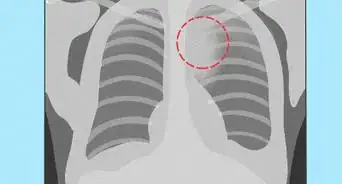

1Know what to expect during a chest X-ray. A chest X-ray is one of the most common X-ray procedures and is used to produce images of the heart, lungs, airways, blood vessels, and the bones of the spine and chest. It's normally used for diagnosing problems such as:[8]

- Shortness of breath, bad or persistent cough, and chest pain or injury.

- It can also be used for diagnosing or monitoring conditions such as pneumonia, heart failure, emphysema, lung cancer, and fluid or air around the lungs.